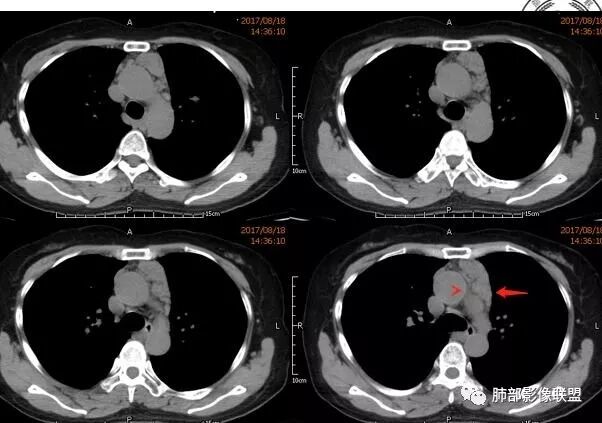

3.纵隔淋巴结肿大?,以主动脉弓为界向上向下增大。

wonderful

多发气囊,气囊内可见血管进入,因患者眼干伴类风湿,可能有干燥综合征,那LIP可能性大。因为不是育龄期发病,可排除LAM。患者左纵膈淋巴结肿大,且有融合趋势,结合左下肺病灶,考虑合并恶性肿瘤,淋巴瘤?鉴别结节病

左肺下叶混杂密度病灶,其内可见空泡,周围ggo清楚,考虑浸润性腺癌。双肺散在多发薄壁囊腔和实性结节,以胸膜下及血管旁分布位于,气囊可见血管贴边征,双肺小叶间隔及中央间质增厚,局部可见磨玻璃影及树芽征,纵隔内淋巴结肿大,考虑LIP

综上,考虑左下肺浸润性腺癌+LIP

双肺多发散在斑片状磨玻璃密度影及大小不等的薄壁含气囊腔,下肺相对较多较大。双肺多发结节,界清,边缘光滑,分叶不明显。右肺下叶前外基底段散在斑片树芽。前上纵膈偏左侧不规则软组织团块,密度不均,其内可见不规则纤维样低密度,周围簇状小淋巴结。考虑1淋巴细胞间质性肺炎。2考虑纵膈胸腺淋巴瘤。